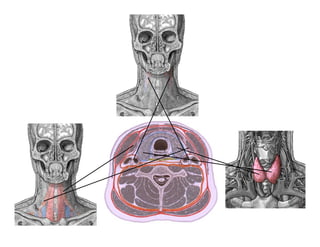

Este documento describe los principios de construcción de la arquitectura craneofacial, incluyendo el metamerismo, la simetría y la paquimería. Explica la organización peri-cavitaria del cráneo a través de columnas y vigas, y analiza las diferentes fascias profundas del cuello. También destaca la importancia de conocer la irrigación ósea con orientación quirúrgica, mencionando los principales aportes vasculares y suplementarios así como el origen, trayecto y retorno venoso de la carót